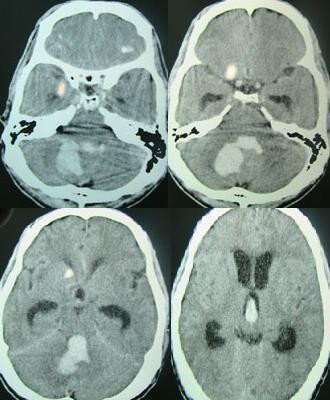

"Левая рука и нога уже совсем не слушаются, еще немеют и как будто одеревенели," - беспокойный взгляд пациента был направлен на невролога, собиравшего анамнез пострадавшего. Доктор поинтересовался, как давно это появилось. "Уже два дня, может и три," - пациент собирался с мыслями, а потом добавил, "я-то думал, что пройдет, потому что сила то исчезала, то появлялась." Доктор тяжело вздохнул и распорядился отправить больного на РКТ головного мозга.

Выйдя из пультовой кабинета РКТ врач вынес свой вердикт - ишемический инсульт в бассейне правой СМА. Пациента госпитализировали в отделение нейрореанимации.

При геморрагическом инсульте чаще всего виноват участок истончения стенки сосуда - аневризма. При повышении артериального давления, к примеру после семейной ссоры, в области аневризмы происходит разрыв и кровоизлияние. Это происходит резко, поэтому и признаки появляются внезапно. "Как будто ломом ударили по голове" - так описывают свое состояние больные. Изредка кровоизлияние протекает незаметно, единственное, что может беспокоить - легкое головокружение. В таком случае инсульт диагностируется случайно - как находка при проведении РКТ головного мозга. Лечение зависит от локализации катастрофы, если есть возможность, то пациенту проводится нейрохирургическая операция с трепанацией черепа и механическим удалением гематомы. При недоступности участка кровоизлияния в головном мозге для хирургического вмешательства проводится лечение в условиях нейрореанимации. Один из вариантов предотвращения кровоизлияния - использование методик рентгенхирургии. В данном случае аневризма заполняется специальной мелкой стружкой, таким образом укрепляется стенка в месте ее истончения.